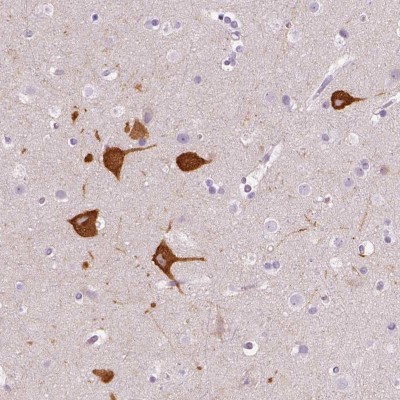

Supportive validation

- Submitted by

- Novus Biologicals (provider)

- Main image

- Experimental details

- Immunohistochemistry-Paraffin: FAM163B Antibody [NBP2-57157] - Immunohistochemical staining of human cerebral cortex shows cytoplasmic positivity in neuronal cells.